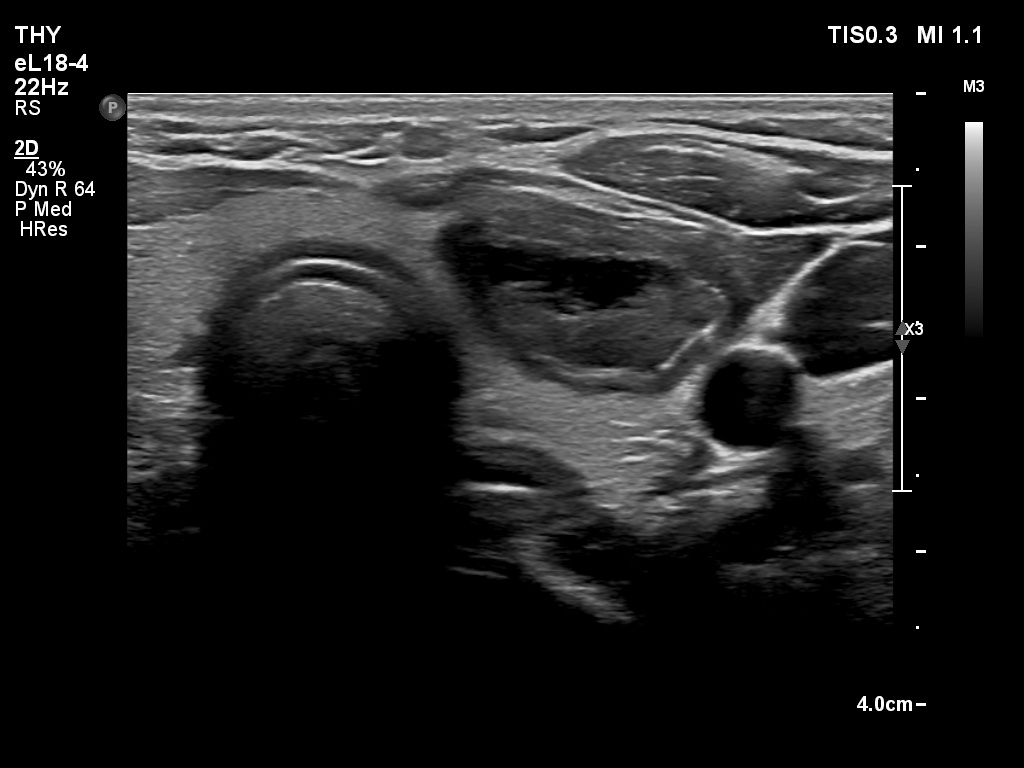

First examination (first and second rows of images)

Clinical presentation: A 39-yr old woman was referred for evaluation of a thyroid cyst which has refilled twice in the past. On the last aspiration, 2 years ago the maximal diameter of the nodule was 24 mm.

Palpation: no abnormality.

Laboratory test: 2.71 mIU/L.

Ultrasonography. The thyroid was echonormal. There was a central-type cystic nodule in the left lobe. The solid portion was echonormal-minimally hypoechoic. The lesion showed back wall cystic figures.Cytology was performed from the lesion in the left lobe and resulted in benign, cystic-colloid goiter.

Suggestion. Ultrasound in two years, in the event of complaints at once. If the cyst would recur ethanol sclerotherapy is advised.